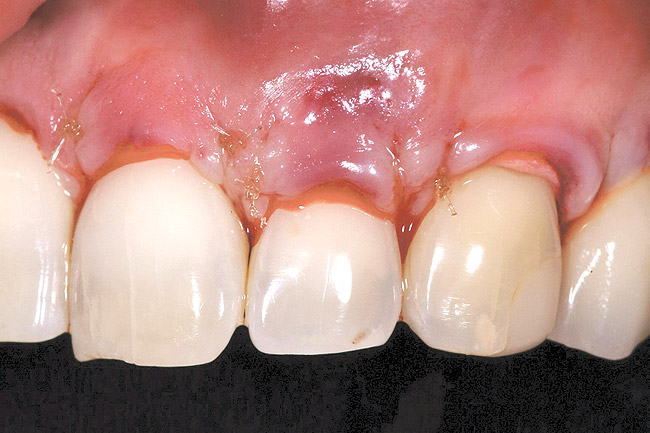

The 2.5-week postoperative clinical view can be seen in Figure 10 through Figure 12. Note the rapid soft tissue healing and maturation. At 6-weeks postoperative, tissue plasty was accomplished to blend the thickened keratinized tissue, in addition to placement of class V composite restorations at teeth Nos. 5, 6, and 11 to create a new restorative margin on the root surfaces.

Figure 10  Case One The 2.5-week postoperative view, maxillary anterior.

Figure 10

Figure 11  Case One The 2.5-week postoperative view, maxillary right.

Figure 11

Figure 12  Case One The 2.5-week postoperative view, maxillary left.

Figure 12